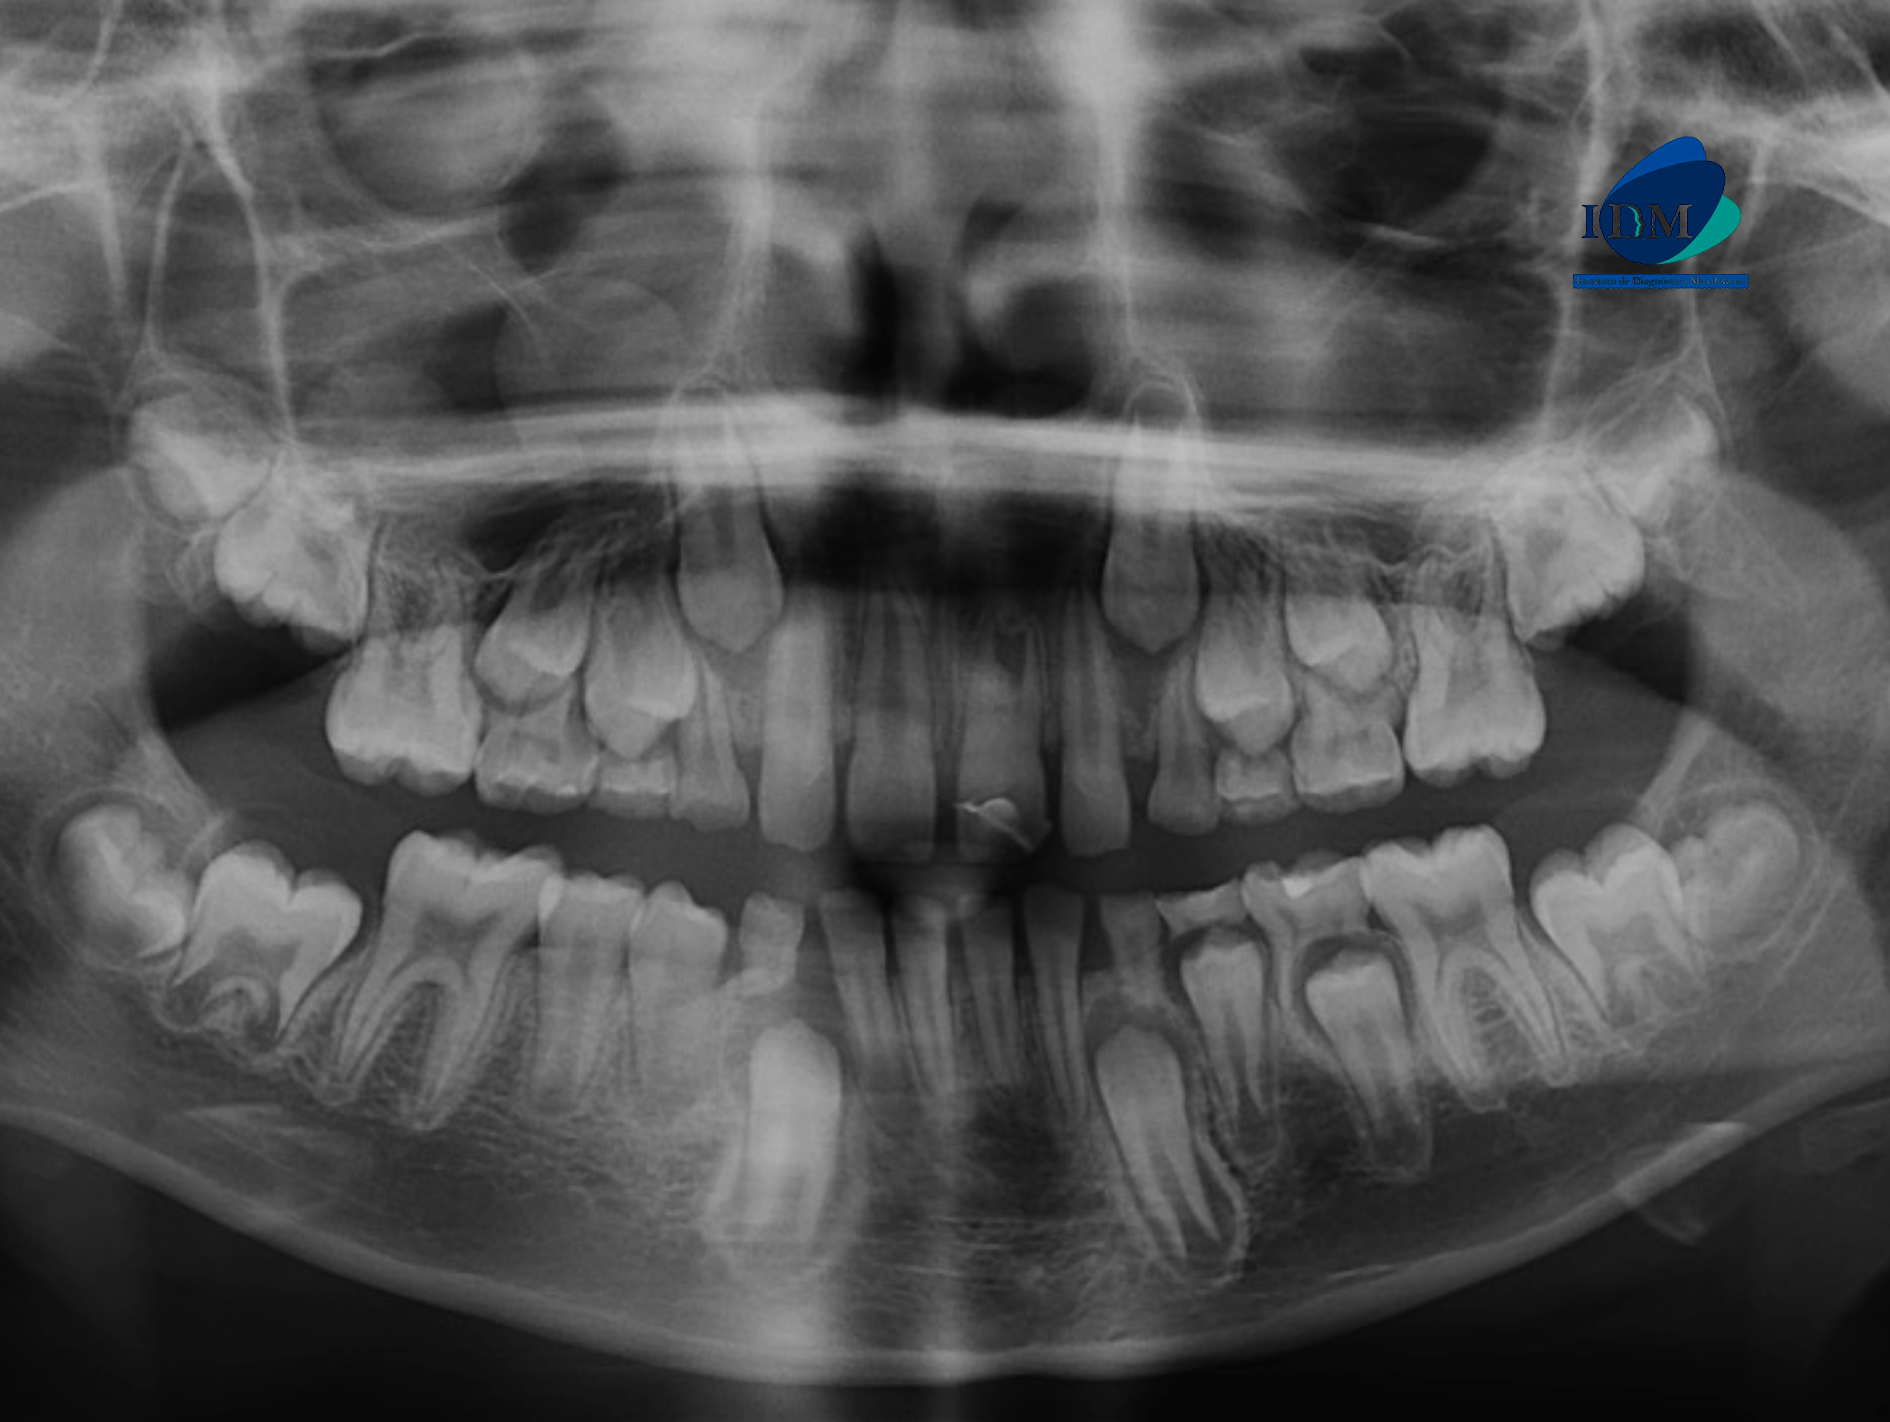

En la radiografía panorámica (Figura 1), se observa pieza 21 con material restaurador coronal, obliteración parcial cámara y conducto radicular.

Radiografia Panorámica